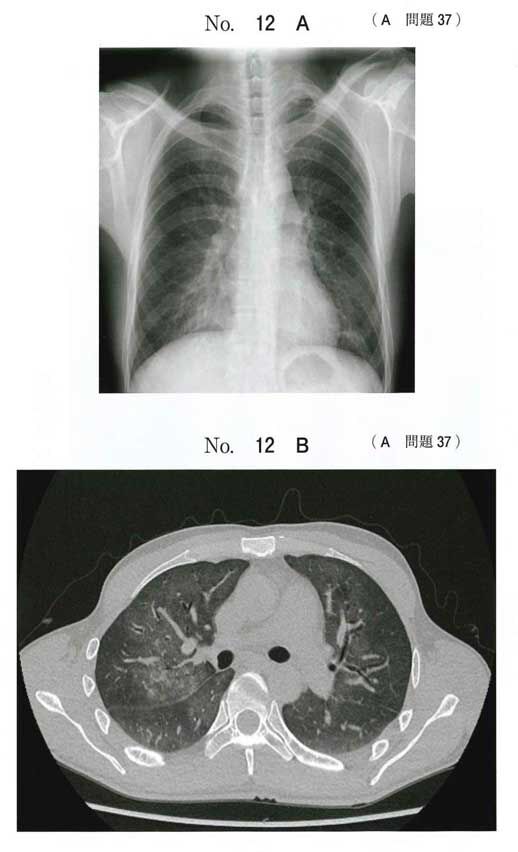

抹消がスペアされたすりガラス陰影はニューモシスチス肺炎に典型的、ですが 上肺野の画像を出さないのはちょっと意地悪かなぁと思ってしまいます。 この状態だとサイトメガロ感染症は 合併 していてもおかしくはありませんが、最も考えられるのはニューモシスチス肺炎 1 2 診断のアプローチ 治 療 ⑴ どのようなときに疑うか 体動時の息切れ、咳嗽、発熱、呼吸困難が出現したとき。胸部x線写真の陰影が出現する 以前に、肺拡散能や動脈血酸素分圧が低下することもある。5肺・胸膜 (10)ニュウモシスティス肺炎病理コア画像 5肺・胸膜 (10)ニュウモシスティス肺炎 ミクロ像(HE弱拡大):TBLBの材料。 肺胞内に好酸性(エオジンに染まる)泡沫状の滲出物を認める。 画像をクリックすると拡大表示します。

画像診断 41巻2号 (21年1月) ニューモシスチス肺炎(PCP)とサイトメガロウイルス肺炎(CMVP)はHRCT上,いずれも広範なすりガラス影が高頻度であるが,前者ではコンソリデーションや結節の頻度は低いのに対して,後者ではいずれも少なからずみニューモシスチス肺炎の新展開 ニューモシスチス肺炎(以下、pcp)は、aidsなど高度の免疫低下者に合併する重い 日和見肺炎として知られて来ましたが、その診断・治療方法は大体確立し、問題として は一段落といった様相です。画像 (1) 臨床検査 (0) 表 (0) 肺胞気動脈血酸素分圧較差 ニューモシスチス肺炎 Pneumocystis jiroveciiは免疫抑制患者,特にヒト免疫不全ウイルス(HIV)感染患者およびコルチコステロイドの全身投与を受けている患者における肺炎の一般的な起因菌である。症状と

逆に、aids患者の気胸を見たときには、ニューモシスチス肺炎を疑う。 亜急性〜慢性(28週)の経過で発症。一方でnonhivは急性。 aids患者の60%がpcp発症で発見。 nonhivpcpは死亡率3550%。hivpcpは死亡率10%。 症例 hiv陽性患者のpcp画像所見2症例 Kerley line,hilar haze, 気管支血管周囲肥厚 :左心不全 Tram line:気管支拡張症,気管支炎,びまん性汎細気管支炎 (画像引用元 不明) 47 ニューモシスチス肺炎のスリガラス影 48 ニューモシスチス肺炎のスリガラス影 (XPで見える場合) 49>画像所見 : 両下肺野優位で微細な網状影とすりガラス影が広がっている。 >診断 : ニューモシスチス肺炎(旧 カリニ肺炎) >解説 : 広範なすりガラス影を示す代表的な疾患としては、 ニューモシスチス肺炎とサイトメガロウイルス肺炎があげられる。

115回医師国家試験問題 A37 ニューモシスチス肺炎 今年の医師国家試験を解いてみました